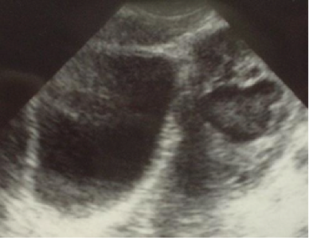

Image 2. This ultrasound image depicts a complex left ovarian mass consistent with TOA. Image reproduced with permission, ERPocketBooks.com.

Pelvic ultrasound is warranted if TOA is suspected or the diagnosis is unclear. It is particularly useful to rule out other diseases that may present with pelvic pain such as a ruptured ovarian cyst (free fluid in the pouch of Douglas) or an ovarian torsion (absence of blood flow to one ovary on pelvic ultrasound with doppler).

The patient’s physical exam was concerning for PID, and the Emergency Medicine physician ordered a pelvic ultrasound to evaluate for a TOA. The ultrasound demonstrated a 4cm TOA on the right ovary. IV antibiotics were started and she was admitted to the Gynecology service. After a couple of days she improved and was transitioned to oral antibiotics and discharged home.